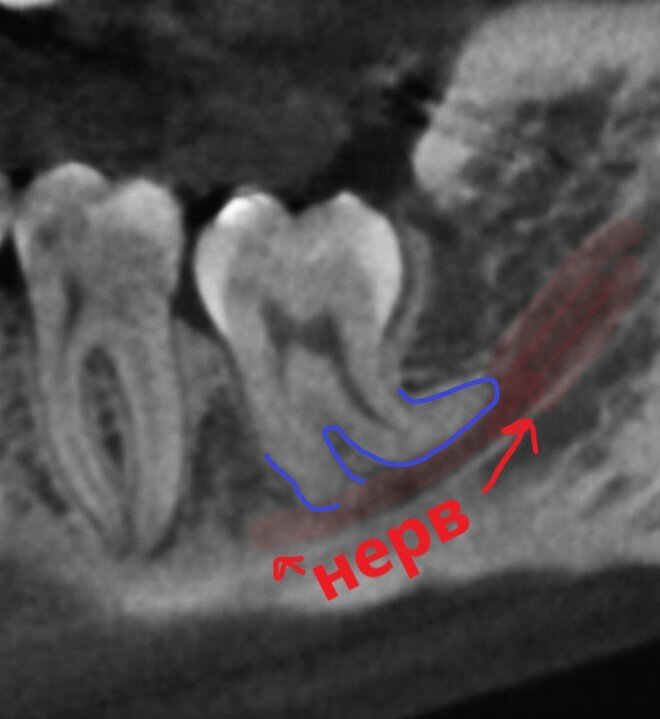

А не желаете рискнуть нервом и чувствительностью?

А вот и захватничество видно.

Бедный нижнечелюстной нерв поджался и терпит. Как и хозяйка данного зуба.